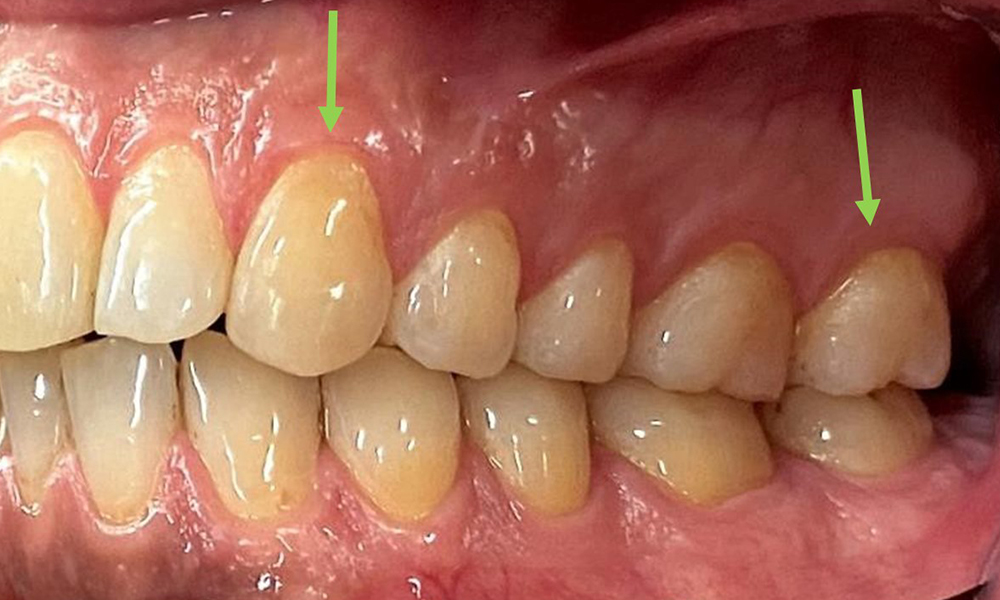

Close-up view of teeth

Fig. 5: Close-up view of teeth 45 to 47. The green arrows show dental attrition and erosions of the buccal cusps with partial enamel loss, © Dr R. Krapf

The patient has full dentition with a total of 28 teeth. There were noteworthy erosions and attritions. (Fig. 4, Fig. 5). Due to bruxism, the patient has been wearing a splint with an adjusted bite block at night for many years. The erosions were caused by long-term consumption of isotonic beverages. No periodontal bone loss or active caries were observed.

Full complement of adult teeth with no caries or radiologically recognizable bone loss was observed (Fig. 6). Radiological enamel and cusp loss were particularly evident on 36 and 37.